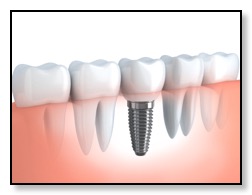

There are two basic types of bone grafting for dental implants. The most common one is after you have a tooth extracted, or if you lost a tooth awhile back. There could be insufficient bone support in such scenarios and thus a bone graft is needed. (See diagram above.) Dr. Tsai will numb the gum before making an incision to expose the area requiring the graft, or if the tooth was just extracted, then she will gently push the gum back to expose the existing bone. She will then place the graft, anchoring it in place if necessary, before covering it with a membrane and suturing the gum back in place. You will be given instructions on how to care for the bone graft site, and how to keep it clean. Bone grafts generally need to be left to heal for several months, although, if the amount of bone grafted was relatively small, it may be possible to place the implant at the same time.

Once the bone is heal, Dr. Tsai will place the implant, allow that to integrate with the bone, and then restore with an Abutment and Crown.